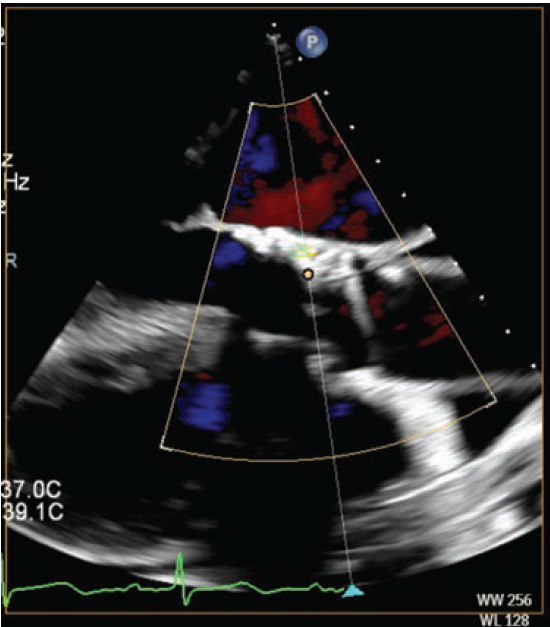

A 7 French (Fr), 45 cm sheath was inserted via the right femoral artery. The PVL was crossed with a 7 Fr multipurpose guide catheter, a Berenstein catheter in a mother-daughter technique, and a Minamo coronary wire (Asahi Intecc). The Berenstein catheter was then advanced into the left ventricle and confirmed with fluoroscopy to be completely outside the valve frame (Figure 3). A Confida wire (Medtronic) was placed in the left ventricular apex, after which the Berenstein catheter was removed. A 7 Fr Railway sheathless access system (Cordis) was utilized to assist the multipurpose guide in crossing into the left ventricle, followed by deployment of an 8 mm Amplatzer Vascular Plug II (Abbott). This was selected to ensure coverage of the two jets on either side of the calcific annular nodule with the proximal and distal disks. The plug was successfully deployed reducing the PVL to trace. Intraoperative TEE showed trace PVL (Figure 4).

The patient was discharged on postoperative day 1 and remains fully independent with minimal dyspnea at 8-month follow-up.